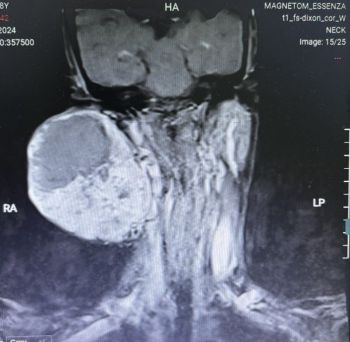

Ung thư không rõ nguyên phát

Ung thư không rõ nguyên phát (UTKRNP) là tình trạng ung thư đã di căn từ một cơ quan khác trong cơ thể nhưng các xét nghiệm ...